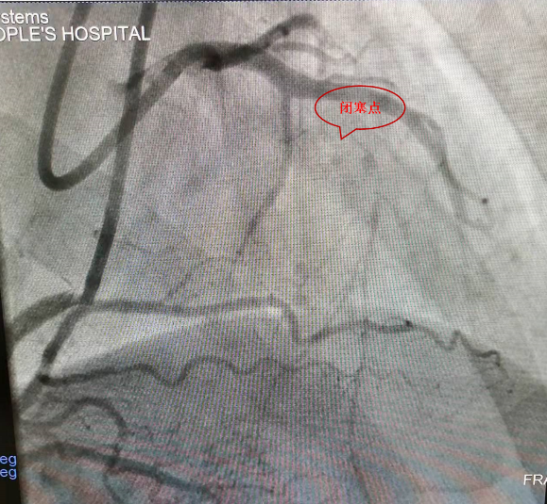

开通血管前造影图像

患者潘先生,曾因心绞痛反复发作住院诊治,行冠状动脉造影检查提示二支血管病变,其中左前降支近段慢性完全闭塞病变,闭塞段病变入口位于分叉处,无残端,曾尝试行冠状动脉介入治疗,正向开通该闭塞血管不成功。